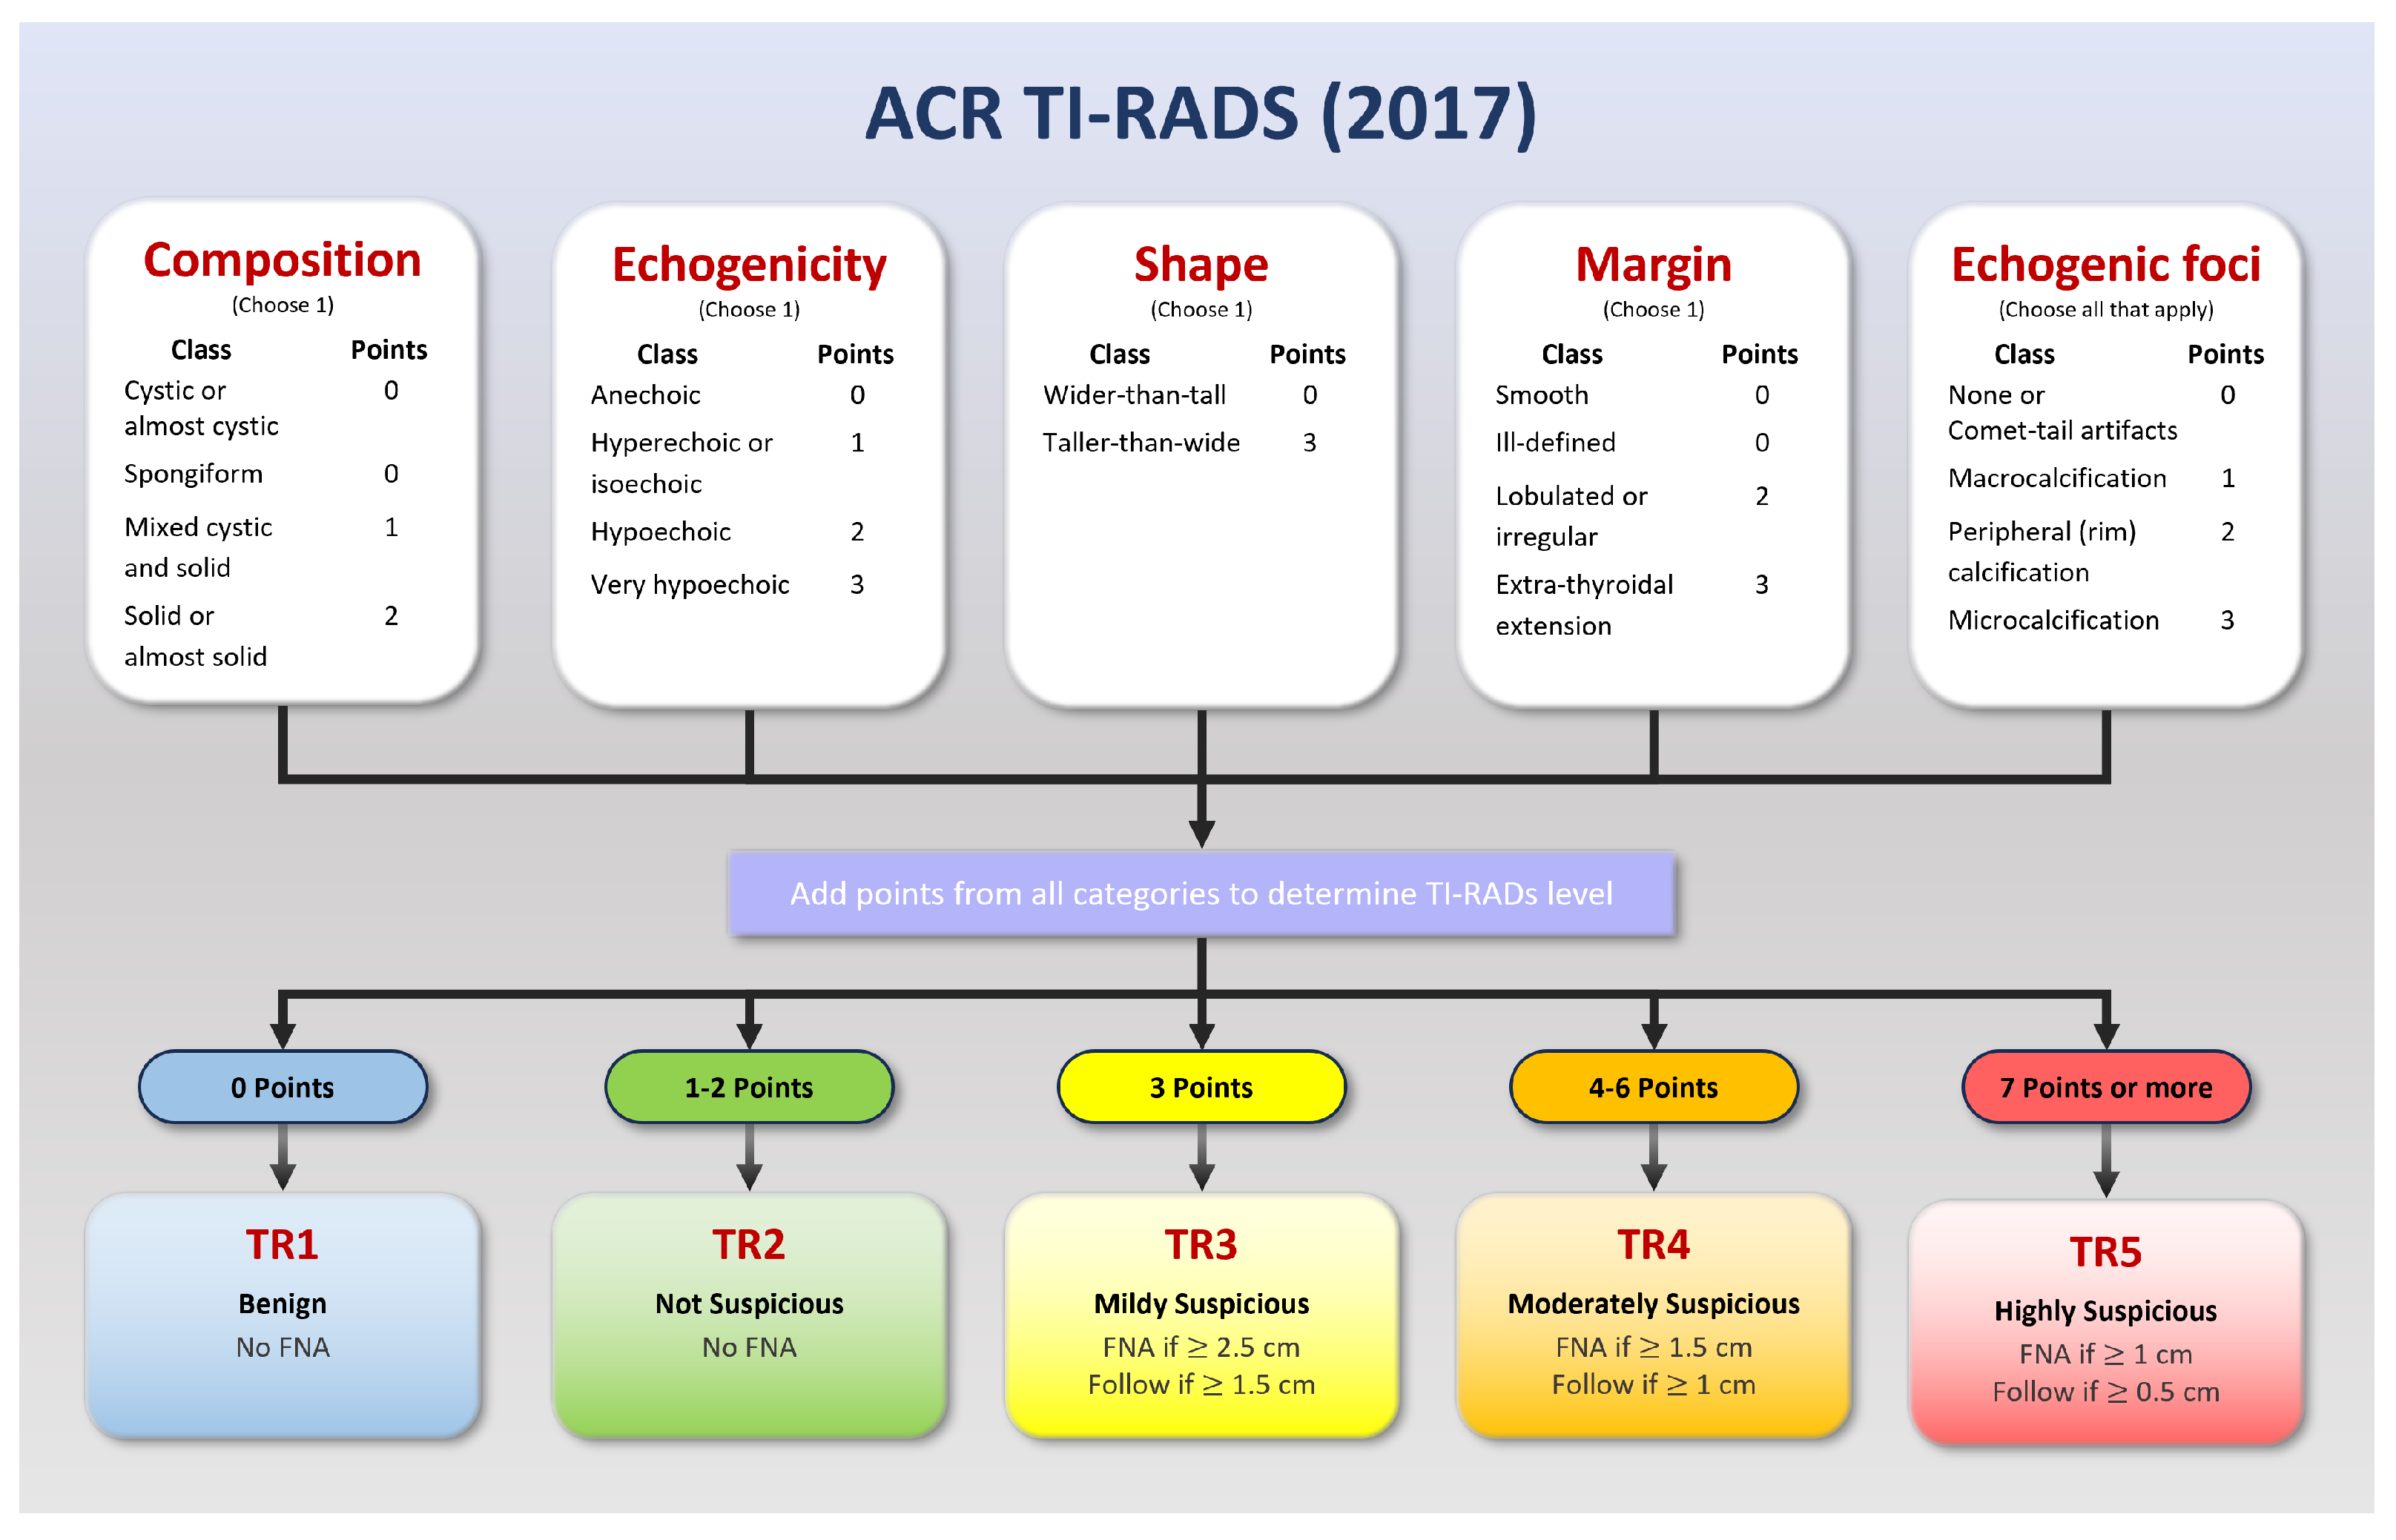

Many ultrasound-based risk stratification systems (RSS) can be employed to gauge the level of malignancy. The American College of Radiology Thyroid Imaging Reporting and Data System (ACR TI-RADS), published in 2017, is one of the most prevalent [

1]. The ACR TI-RADS classifies nodules into five levels (TR1–TR5). Higher levels indicate a need for physicians to perform an FNA (fine-needle aspiration) or thyroid biopsy, while medium levels may lead to follow-up recommendations. The TI-RADS classification system helps prevent over-diagnosis, thus reducing wasted time and cost [

To assess the nature of thyroid nodules, medical professionals commonly utilize the American College of Radiology Thyroid Imaging Reporting and Data System (ACR TI-RADS) [

13]. This system has evolved through multiple revisions, with the latest update being published in 2017 (

Figure 1). TI-RADS is a valuable tool in classifying nodules, assigning scores that range from TR1 to TR5 based on features such as composition, echogenicity, shape, margins, and echogenic foci.

Most individuals will develop thyroid nodules as they age, although the vast majority of these nodules are benign. Some, however, can evolve into cancerous growths, necessitating vigilant monitoring and, in cases where the TI-RADS score is high, procedures such as Fine-Needle Aspiration (FNA) or a thyroid biopsy.

The TI-RADS scoring system provides a robust framework for distinguishing between benign and malignant cases. A lower score, such as TR1, indicates a benign condition, while a higher score is more suggestive of malignancy. The category TR3 is often considered a threshold for initiating follow-up, depending on the nodule’s size (15 mm or larger) [

Figure 1.

ACR TI-RADS 2017: A risk stratification system for thyroid nodules derived from ultrasound findings. This system assigns scores ranging from 1 to 5, where higher scores correspond to an increased probability of malignancy. It plays an essential role in guiding the decision-making process for further evaluation and management of thyroid nodules. Adapted from Tessler [

13].

Figure 1.

ACR TI-RADS 2017: A risk stratification system for thyroid nodules derived from ultrasound findings. This system assigns scores ranging from 1 to 5, where higher scores correspond to an increased probability of malignancy. It plays an essential role in guiding the decision-making process for further evaluation and management of thyroid nodules. Adapted from Tessler [

13].